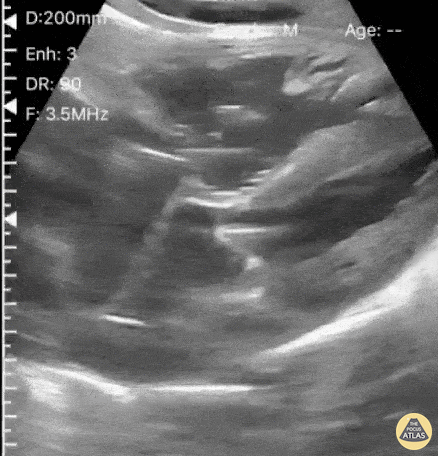

A 33-year-old female presented with cocaine-induced chest pain, dyspnea, and clinical evidence of cariogenic shock. CVL was emergently placed and location confirmed via POCUS Bubble Study. Ultrasound verification of CVL placement is possible by visualizing microbubble artifact in the right atrium following injection of saline through the distal port of the CVL. Dr. Victor Bang. Emergency Physician at Hospital das Clínicas de Marília. Co-founder of Pocus Jedi. @vmjbang